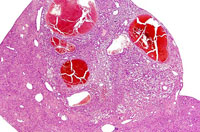

Dilated vascular spaces have replaced hepatic parenchyma in this hemangioma. High magnification shows dilated vascular spaces lined by flattened and sometimes dome-shaped endothelial cells and mild atrophy of the visible hepatic cords.